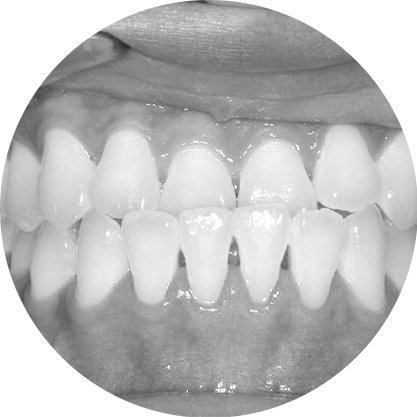

ตัวอย่างในชีวิตจริง